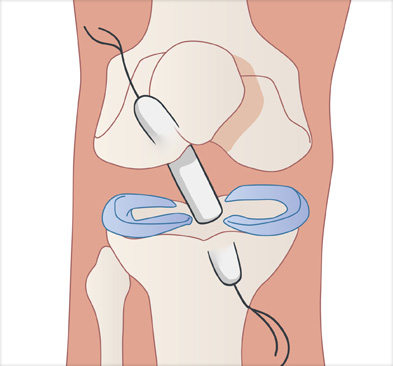

이식한 인대 고정

십자인대 재건술은 손상된 인대를 자가건이나 타가건을 활용해 원래의 인대의 위치에 재건하여 무릎의 기능을 회복시킵니다.